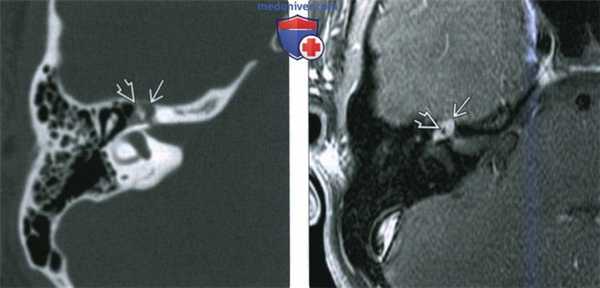

(Слева) При аксиальной КТ в костной окне определяется объемное образование в расширенной ямке коленчатого ганглия с распространением опухоли вдоль переднего барабанного сегмента ЧН VII со смещением слуховых косточек латерально. Наружная поверхность слуховой капсулы истончена ШЛН.

(Справа) При аксиальной МРТ Т1 С+ FS у этого же пациента визуализируется контрастирующаяся ШЛН, расположенная в коленчатом ганглии. Опухоль распространяется вдоль барабанного сегмента ЧН VII и во внутренний слуховой канал по лабиринтному сегменту ЧН VII. Обратите внимание на интрамуральную кисту медиально.